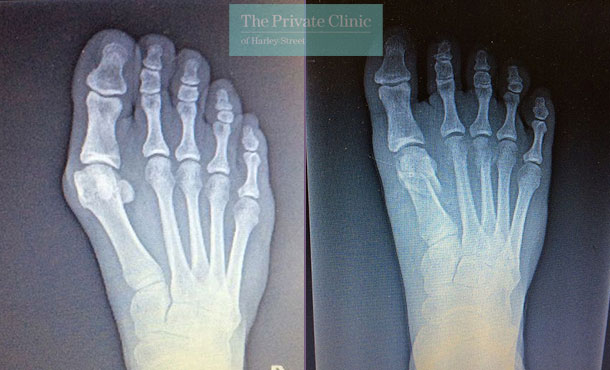

Bunion Correction Before & After Results

Take a look at our various galleries showcasing the amazing results achievable with our exclusive keyhole bunion surgery.